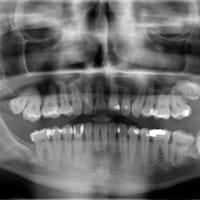

Caries dental tras radiografía boca completa